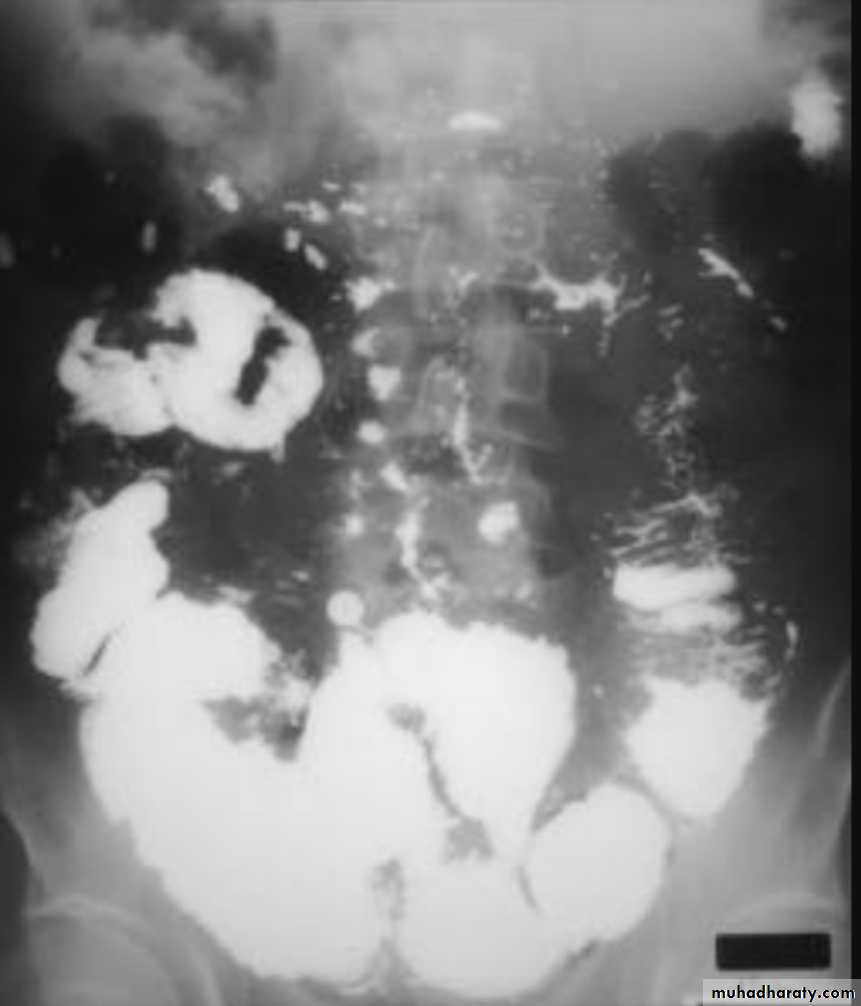

UC

The colon is distended with air

The descending & sigmoid colon are featureless (no haustral pattern)

Thumb printing